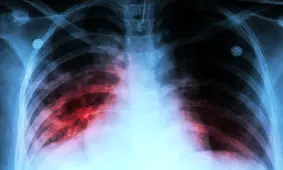

رییس اداره کنترل سل و جذام معاونت بهداشت وزارت بهداشت، درمان و آموزش پزشکی ضمن اشاره به موارد بروز سل در کشور،…

سرپرست دانشگاه علوم پزشکی شهید بهشتی گفت: ۲۲ کشور دنیا در معرض بالاترین میزان شیوع و بروز سل قرار دارند که تقریبا ۱۵…

علیاکبر ولایتی رئیس نهمین کنگره بینالمللی بیماریهای ریوی، مراقبتهای ویژه و سل گفت: ایران در منطقه غرب آسیا و شمال…